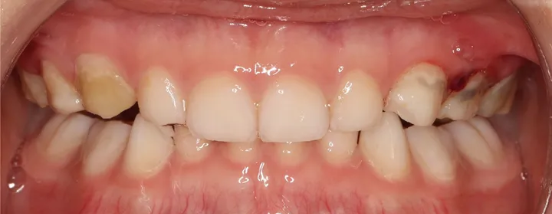

3、地包天的面型,我认为5岁左右就可以开始做,我有的患者最夸张的时候,一对双胞胎的地包天,他爸他妈抱着来的,当然这是一个极极特殊的例子,还是等到孩子能配合的时候再来。

实际上地包天的主要产生原因,他的上颌骨长得小,我们叫上颌发育不足,下颌骨长得比较大,上颌骨是像积木一样,是由很多块骨头拼接在一起,孩子越小的时候,骨缝之间是纤维组织连接。

当我们给外力的时候,纤维组织间的骨缝,很快就被拽开了,因此我们可以移动整个上颌骨的结构,由于这个时期骨缝之间是软的,孩子也不会觉得疼。

这位小朋友是3岁的时候,妈妈带来做早期矫正改善地包天问题的,因为孩子妈妈也是地包天的情况,在我这里做的矫正。

这就不得不想到遗传因素的重要性了,由于孩子妈妈是反颌,并且孩子有躺着喝奶的习惯,妈妈担心孩子以后反颌越来越严重,所以找我一起做了矫正。

我给孩子用的是硅胶个性化功能矫正器,历时1年的矫治时间,地包天问题得到改善。

在这里也要告诉家长们一般5岁以下的婴幼儿地包天,通常并不是真正意义上的骨性地包天,极少数的病例是由于上颌骨发育不足导致的,绝大多数是由于肌功能问题导致的下颌骨位置前移。

当喂养孩子的姿势不对,下颌被引导向前,久而久之下颌骨肌肉功能异常导致下颌髁状突前移,并超过关节结节的限制,实际上,下颌髁状突处于关节脱位的状态。

因此,5岁以下的这种功能性前移造成的前牙地包天问题,使用早期功能矫治器可以得到很好的改善。